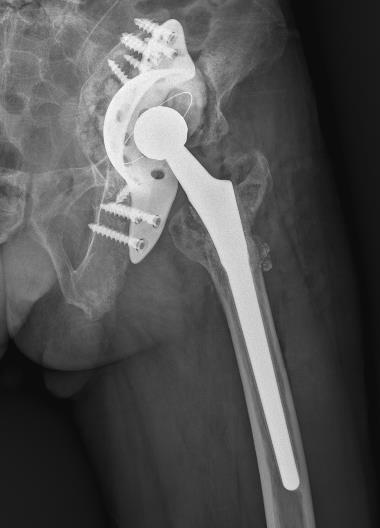

张勇华副院长、骨科二区副主任易治国及骨科团队经充分讨论分析,诊断:双侧全膝关节置换术后假体松动,需行翻修手术,因考虑患者高龄对手术耐受情况及双膝严重程度计划分两次手术完成,先将严重的左侧手术。经充分的术前准备,患者左膝关节置换翻修手术顺利,经过医护人员的精心治疗和康复护理指导,住院期间已在助行器辅助下站立、行走。

术后恢复膝关节稳定性,恢复膝关节正常形态